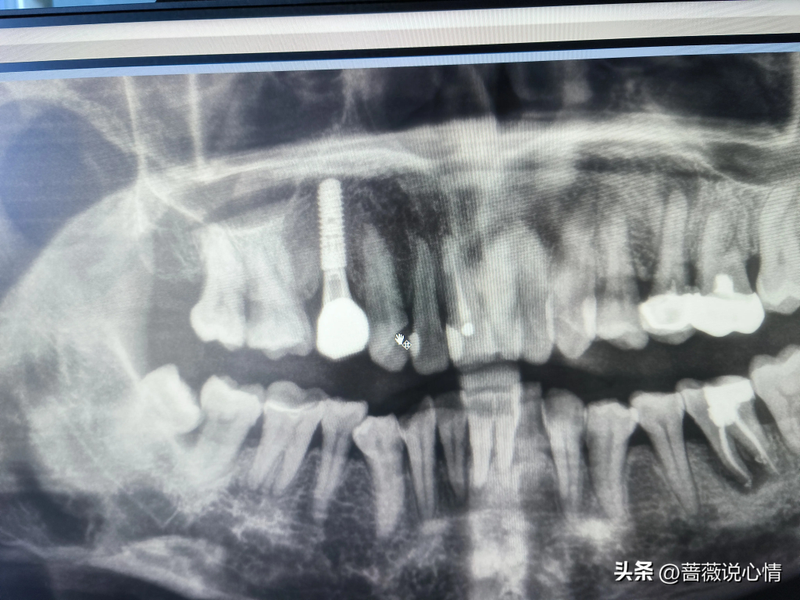

医生通过敲打等方法观察,没发现哪颗牙坏了,于是让我拍了全牙片,这个牙片花60元钱。

悲惨的烂牙

初步判断,医生认为是右下方的智齿把它前面的牙顶坏了。但是一直我都是感觉右上方牙齿在疼痛。